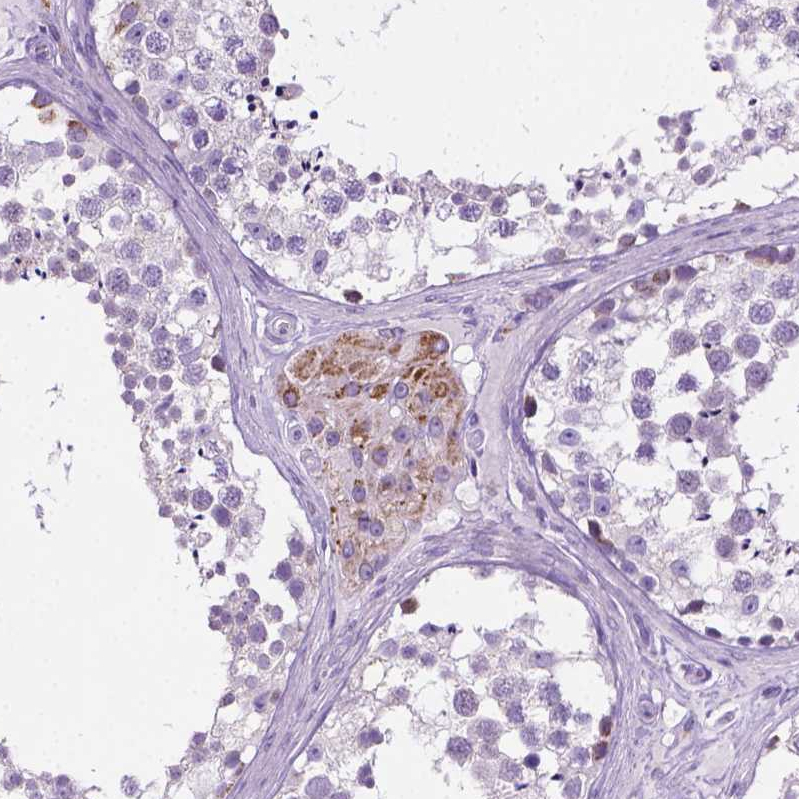

Immunohistochemical staining of human kidney shows moderate cytoplasmic positivity in a subset tubules.